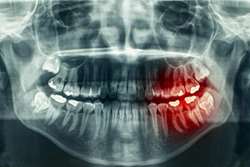

رادیوگرافی پانورامیک (OPG)، یک روش تصویربرداری پیشرفته است که به دندانپزشک این امکان را میدهد تا تمام دندانها، استخوانهای فک بالا و پایین، مفاصل گیجگاهیفکی (TMJ) و حتی بخشی از سینوسها را تنها در یک تصویر مشاهده کند.

- مشاهده وضعیت دندانهای عقل، نهفته یا نیمهنهفته